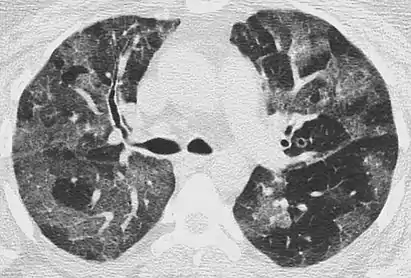

Diffuse

The diffuse pattern typically refers to GGOs in multiple lobes of one or both lungs. Broadly, a diffuse pattern of GGO can be caused by displacement of air with fluid, inflammatory debris, or fibrosis. Cardiogenic pulmonary edema and ARDS are common causes of a fluid-filled lung. Diffuse alveolar hemorrhage is a rarer cause of diffuse GGO seen in some types of vasculitis, autoimmune conditions, and bleeding disorders.[6]

Inflammation and fibrosis can also cause diffuse GGOs. Pneumocystis pneumonia, an infection typically seen in immunocompromised (e.g. patients with AIDS) or immunosuppressed individuals, is a classic cause of diffuse GGOs. Many viral pneumonias and idiopathic interstitial pneumonias can also lead to a diffuse GGO pattern. Radiation pneumonitis, a side effect of pulmonary radiation therapy, can lead to pulmonary fibrosis and diffuse GGOs.[6]